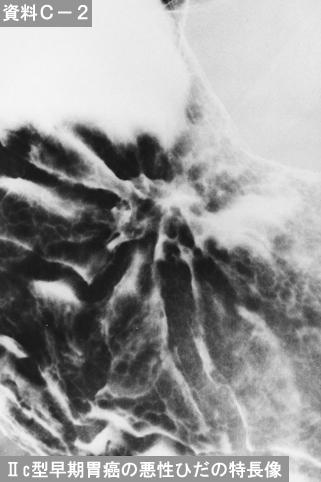

症例提示(所在地,施設名等): 東京都・ 国立がんセンター中央病院と九州がんセンターの共同作成

症例登録日 2014/02/28

画像数 47